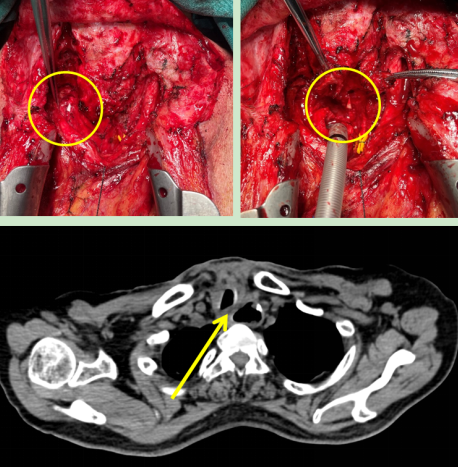

圖2:術中情況(左)喉返神經監測儀監測喉返神經,(右)離斷氣管暴露食管瘺口;

(下)術后CT顯示原氣管食管間瘺口已修補。

在與患者及家屬充分溝通后,胡楊團隊為患者行“經頸部及正中開胸氣管食管瘺修補術,胸大肌帶蒂肌瓣轉移成形術”。術中使用喉返神經監測保護喉返神經,使用帶蒂胸大肌肌瓣隔絕氣管與食管間瘺口。手術順利完成,術后患者未發生聲音嘶啞。

術后第五天,患者突然出現頸部皮下氣腫,經檢查是因為之前院外手術形成的瘢痕,導致氣管缺血壞死,出現氣管吻合口瘺。這是多次手術的患者術后可能出現的問題之一,處理極其困難,若處理不當極易造成慢性胸骨感染,甚至威脅生命。胡楊副主任醫師立馬安排第二次手術,術中使用另一側帶蒂胸大肌肌瓣修補并加固了氣管瘺口,術后復查顯示氣管瘺口成功修補。